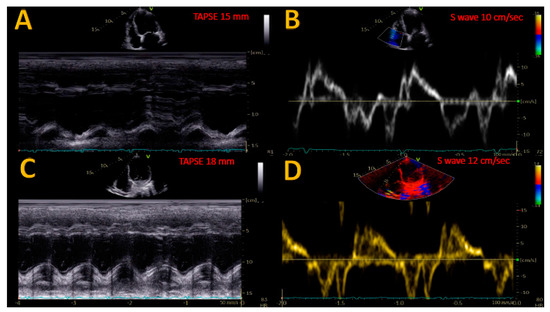

| TAPSE (mm) | 16.6 ± 4.2 | 18.5 ± 3.6 | <0.05 |

| S wave (cm/s) | 10.1 ± 1.8 | 11.3 ± 1.4 | <0.05 |